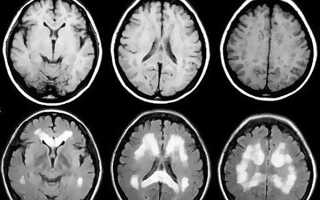

- Магнитно-резонансную томографию.

Если больной жалуется на головную боль при кашле, то первое обследование, которое стоит пройти, – это МРТ головы, в результате которого будет назначено необходимое лечение.

Проведение общего осмотра не позволит определить в живую подобного рода недомогания. В данном случае будет эффективным лишь сдача определенных анализов и компьютерное вмешательство, позволяя точно определить характер опухоли и ее нахождение.